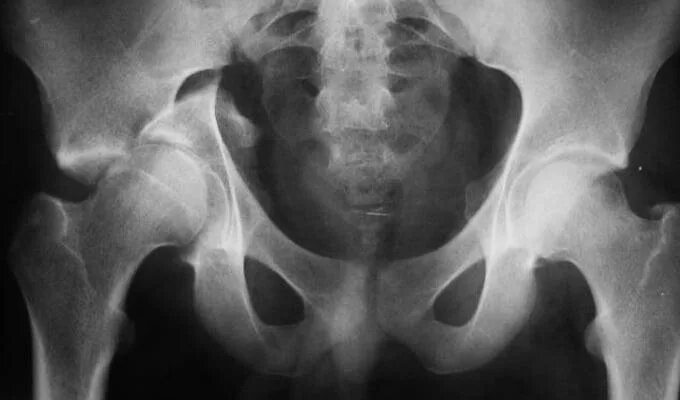

Перелом тазобедренной впадины